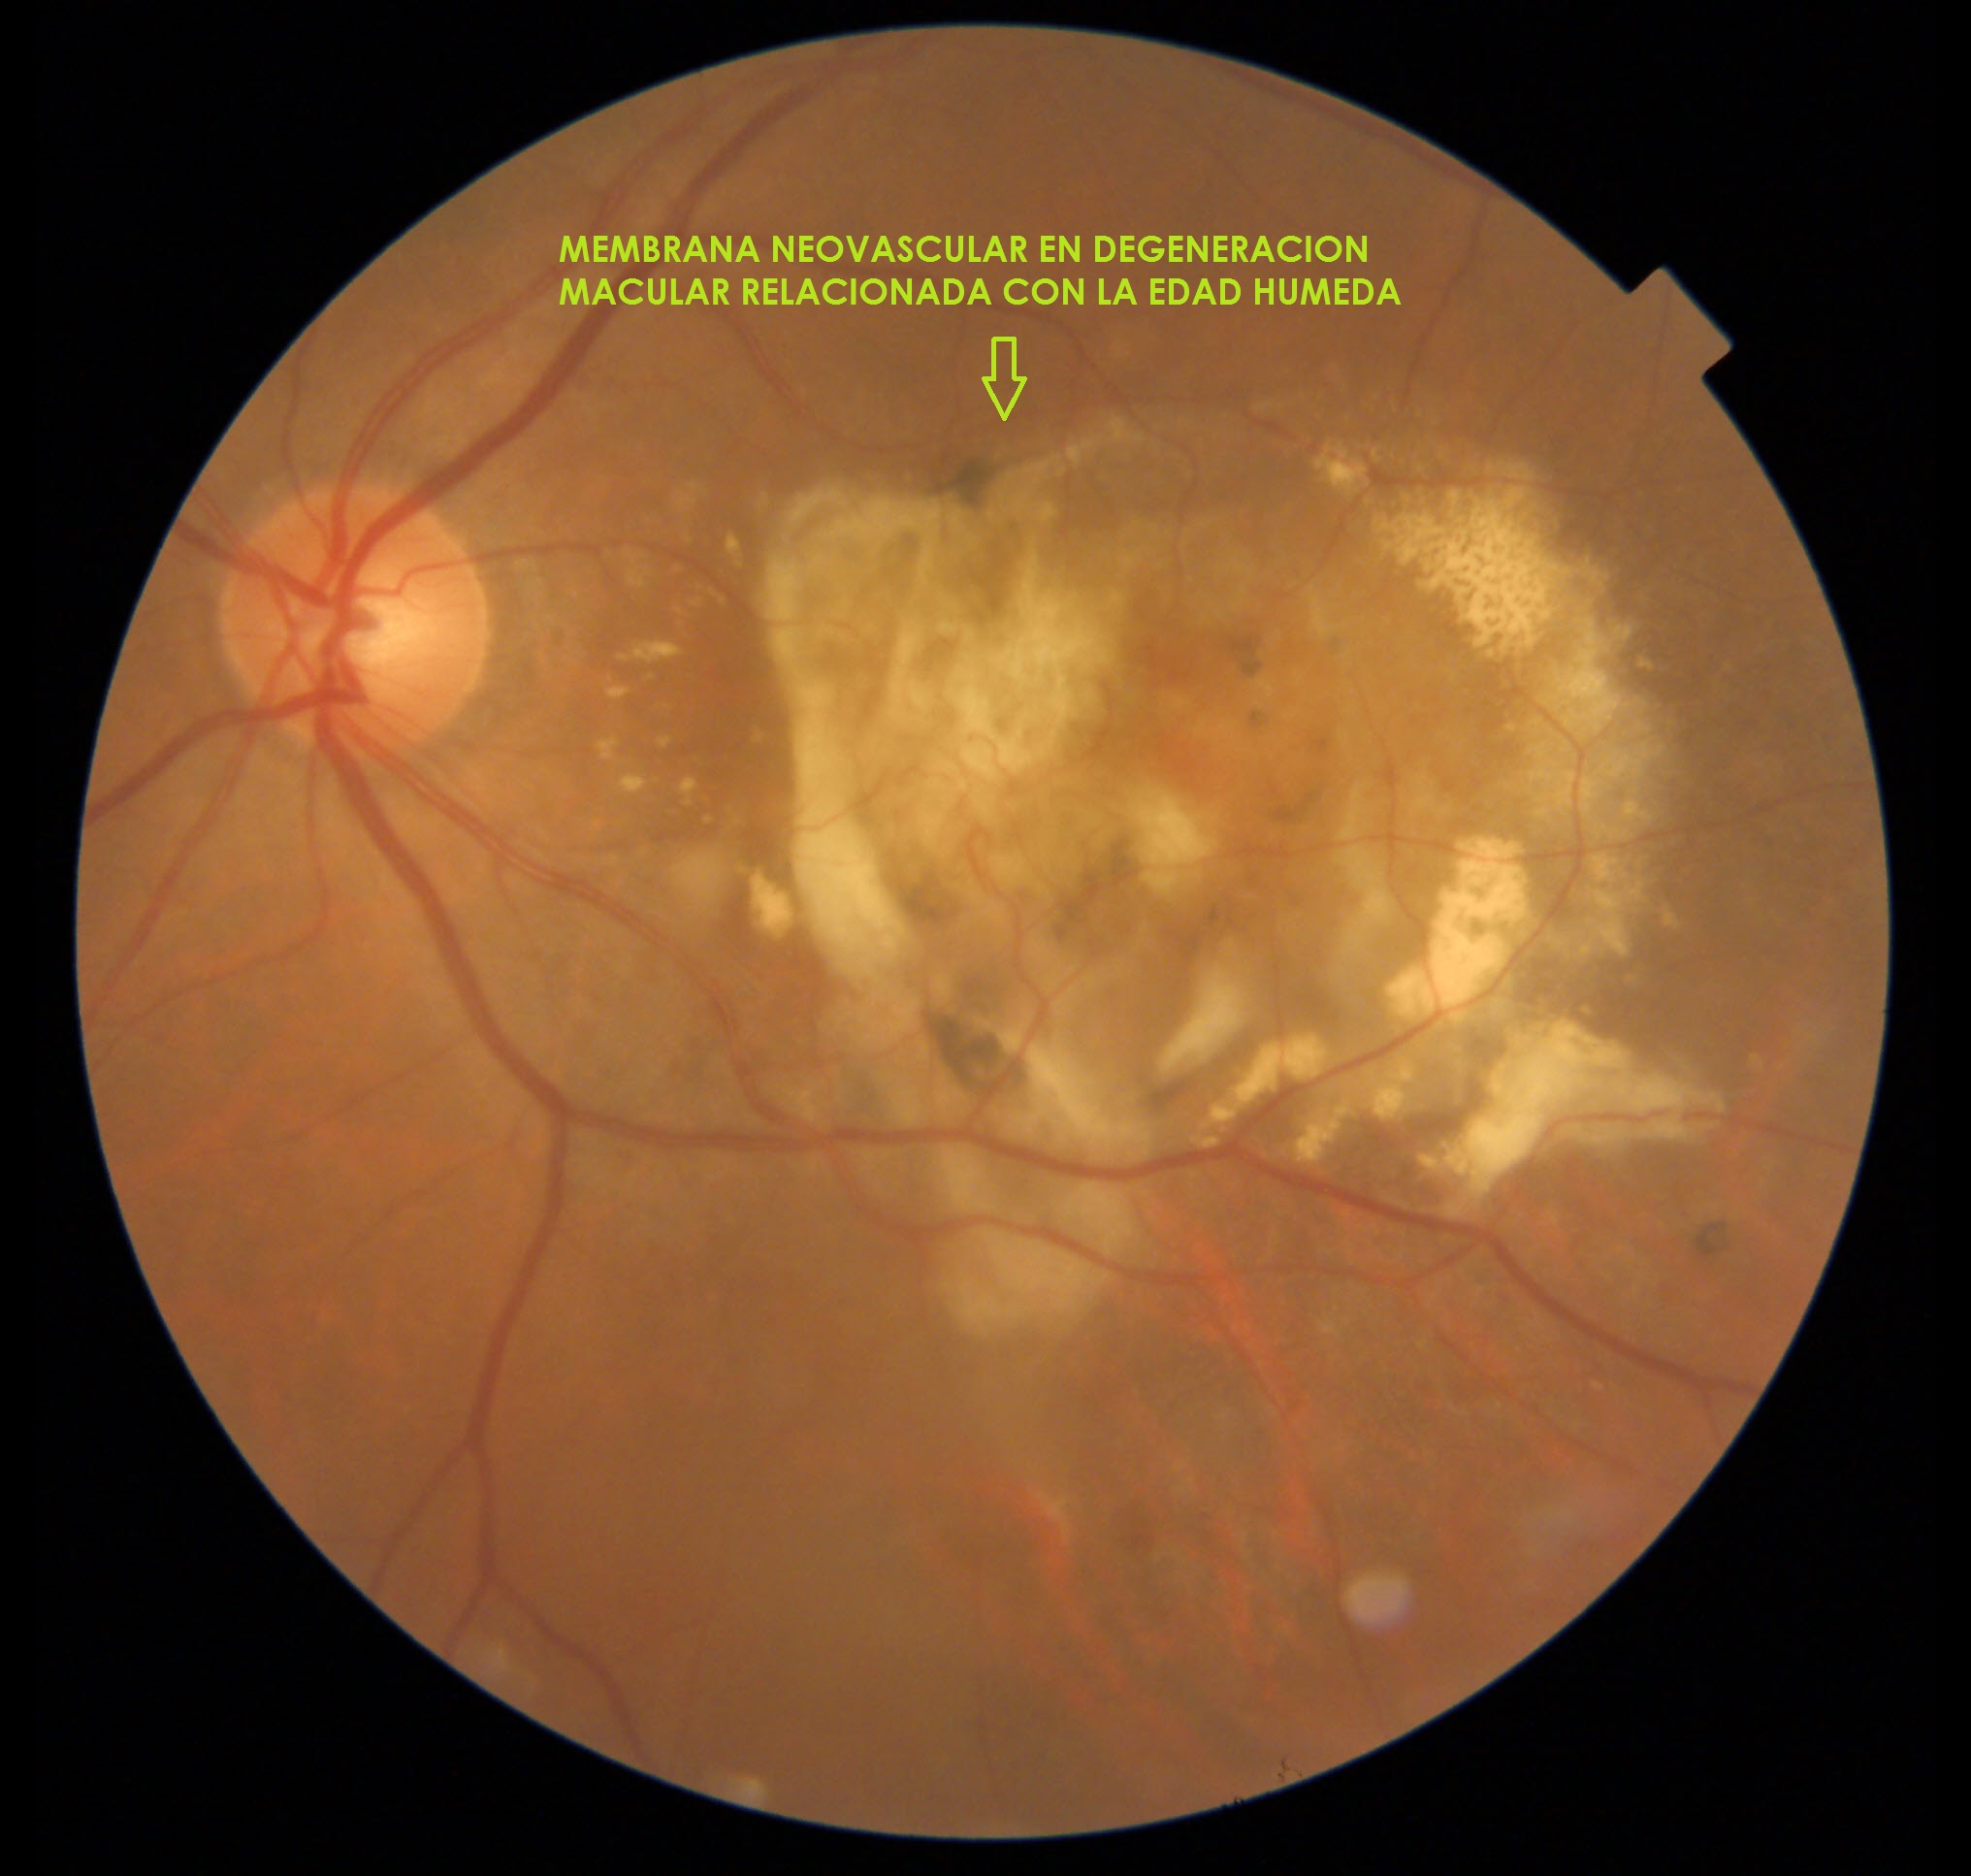

Degeneración Macular Relacionada con la Edad (DMRE)

Es una enfermedad que afecta principalmente a la macula, al presentarse afecta la visión central, la cual es necesaria para conducir automóviles, leer un libro o reconocer caras.

Tiene dos formas de presentación: Seca y Húmeda.

Forma Húmeda:

- Inyecciones intraoculares: La forma húmeda puede tratarse con medicamentos inyectados dentro del ojo (Anti VEGF).